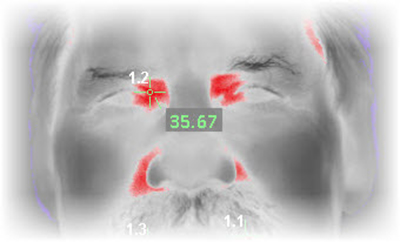

This Screen displays:

- Adjustable warning temperature,

- Place for an identifying name or number for documentation,

- Enable automatic capture when the temperature threshold is displayed,

- Thumbnail tray of saved images,

- Save key for archiving which automatically returns to live feed to save time, and

- Space for notes.

Select the Preferred Palette

Default Palette is

Enhanced Grayscale (red is hot and white is hottest)